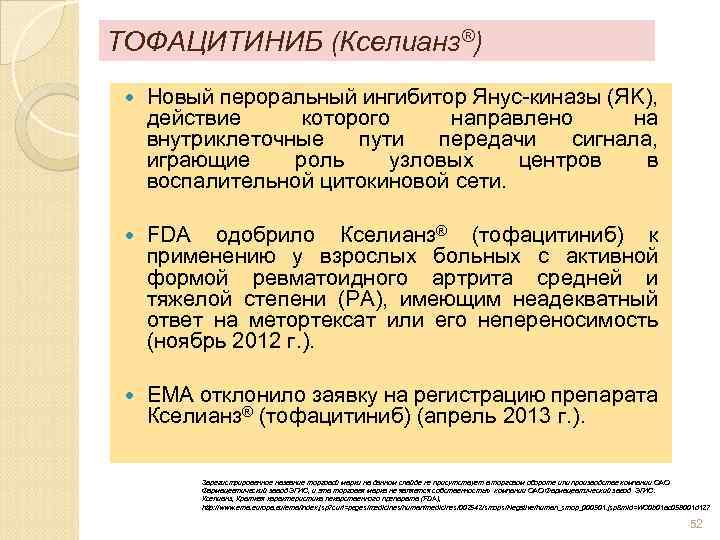

ТОФАЦИТИНИБ (Кселианз®) Новый пероральный ингибитор Янус-киназы (ЯK), действие которого направлено на внутриклеточные пути передачи сигнала, играющие роль узловых центров в воспалительной цитокиновой сети. FDA одобрило Кселианз® (тофацитиниб) к применению у взрослых больных с активной формой ревматоидного артрита средней и тяжелой степени (РA), имеющим неадекватный ответ на метортексат или его непереносимость (ноябрь 2012 г. ). EMA отклонило заявку на регистрацию препарата Кселианз® (тофацитиниб) (апрель 2013 г. ). Зарегистрированное название торговой марки на данном слайде не присутствует в торговом обороте или производстве компании ОАО Фармацевтический завод ЭГИС, и эта торговая марка не является собственностью компании ОАО Фармацевтический завод ЭГИС. Кселианз, Краткая характеристика лекарственного препарата (FDA), http: //www. ema. europa. eu/ema/index. jsp? curl=pages/medicines/human/medicines/002542/smops/Negative/human_smop_000501. jsp&mid=WC 0 b 01 ac 058001 d 127 52

ТОФАЦИТИНИБ (Кселианз®) Новый пероральный ингибитор Янус-киназы (ЯK), действие которого направлено на внутриклеточные пути передачи сигнала, играющие роль узловых центров в воспалительной цитокиновой сети. FDA одобрило Кселианз® (тофацитиниб) к применению у взрослых больных с активной формой ревматоидного артрита средней и тяжелой степени (РA), имеющим неадекватный ответ на метортексат или его непереносимость (ноябрь 2012 г. ). EMA отклонило заявку на регистрацию препарата Кселианз® (тофацитиниб) (апрель 2013 г. ). Зарегистрированное название торговой марки на данном слайде не присутствует в торговом обороте или производстве компании ОАО Фармацевтический завод ЭГИС, и эта торговая марка не является собственностью компании ОАО Фармацевтический завод ЭГИС. Кселианз, Краткая характеристика лекарственного препарата (FDA), http: //www. ema. europa. eu/ema/index. jsp? curl=pages/medicines/human/medicines/002542/smops/Negative/human_smop_000501. jsp&mid=WC 0 b 01 ac 058001 d 127 52